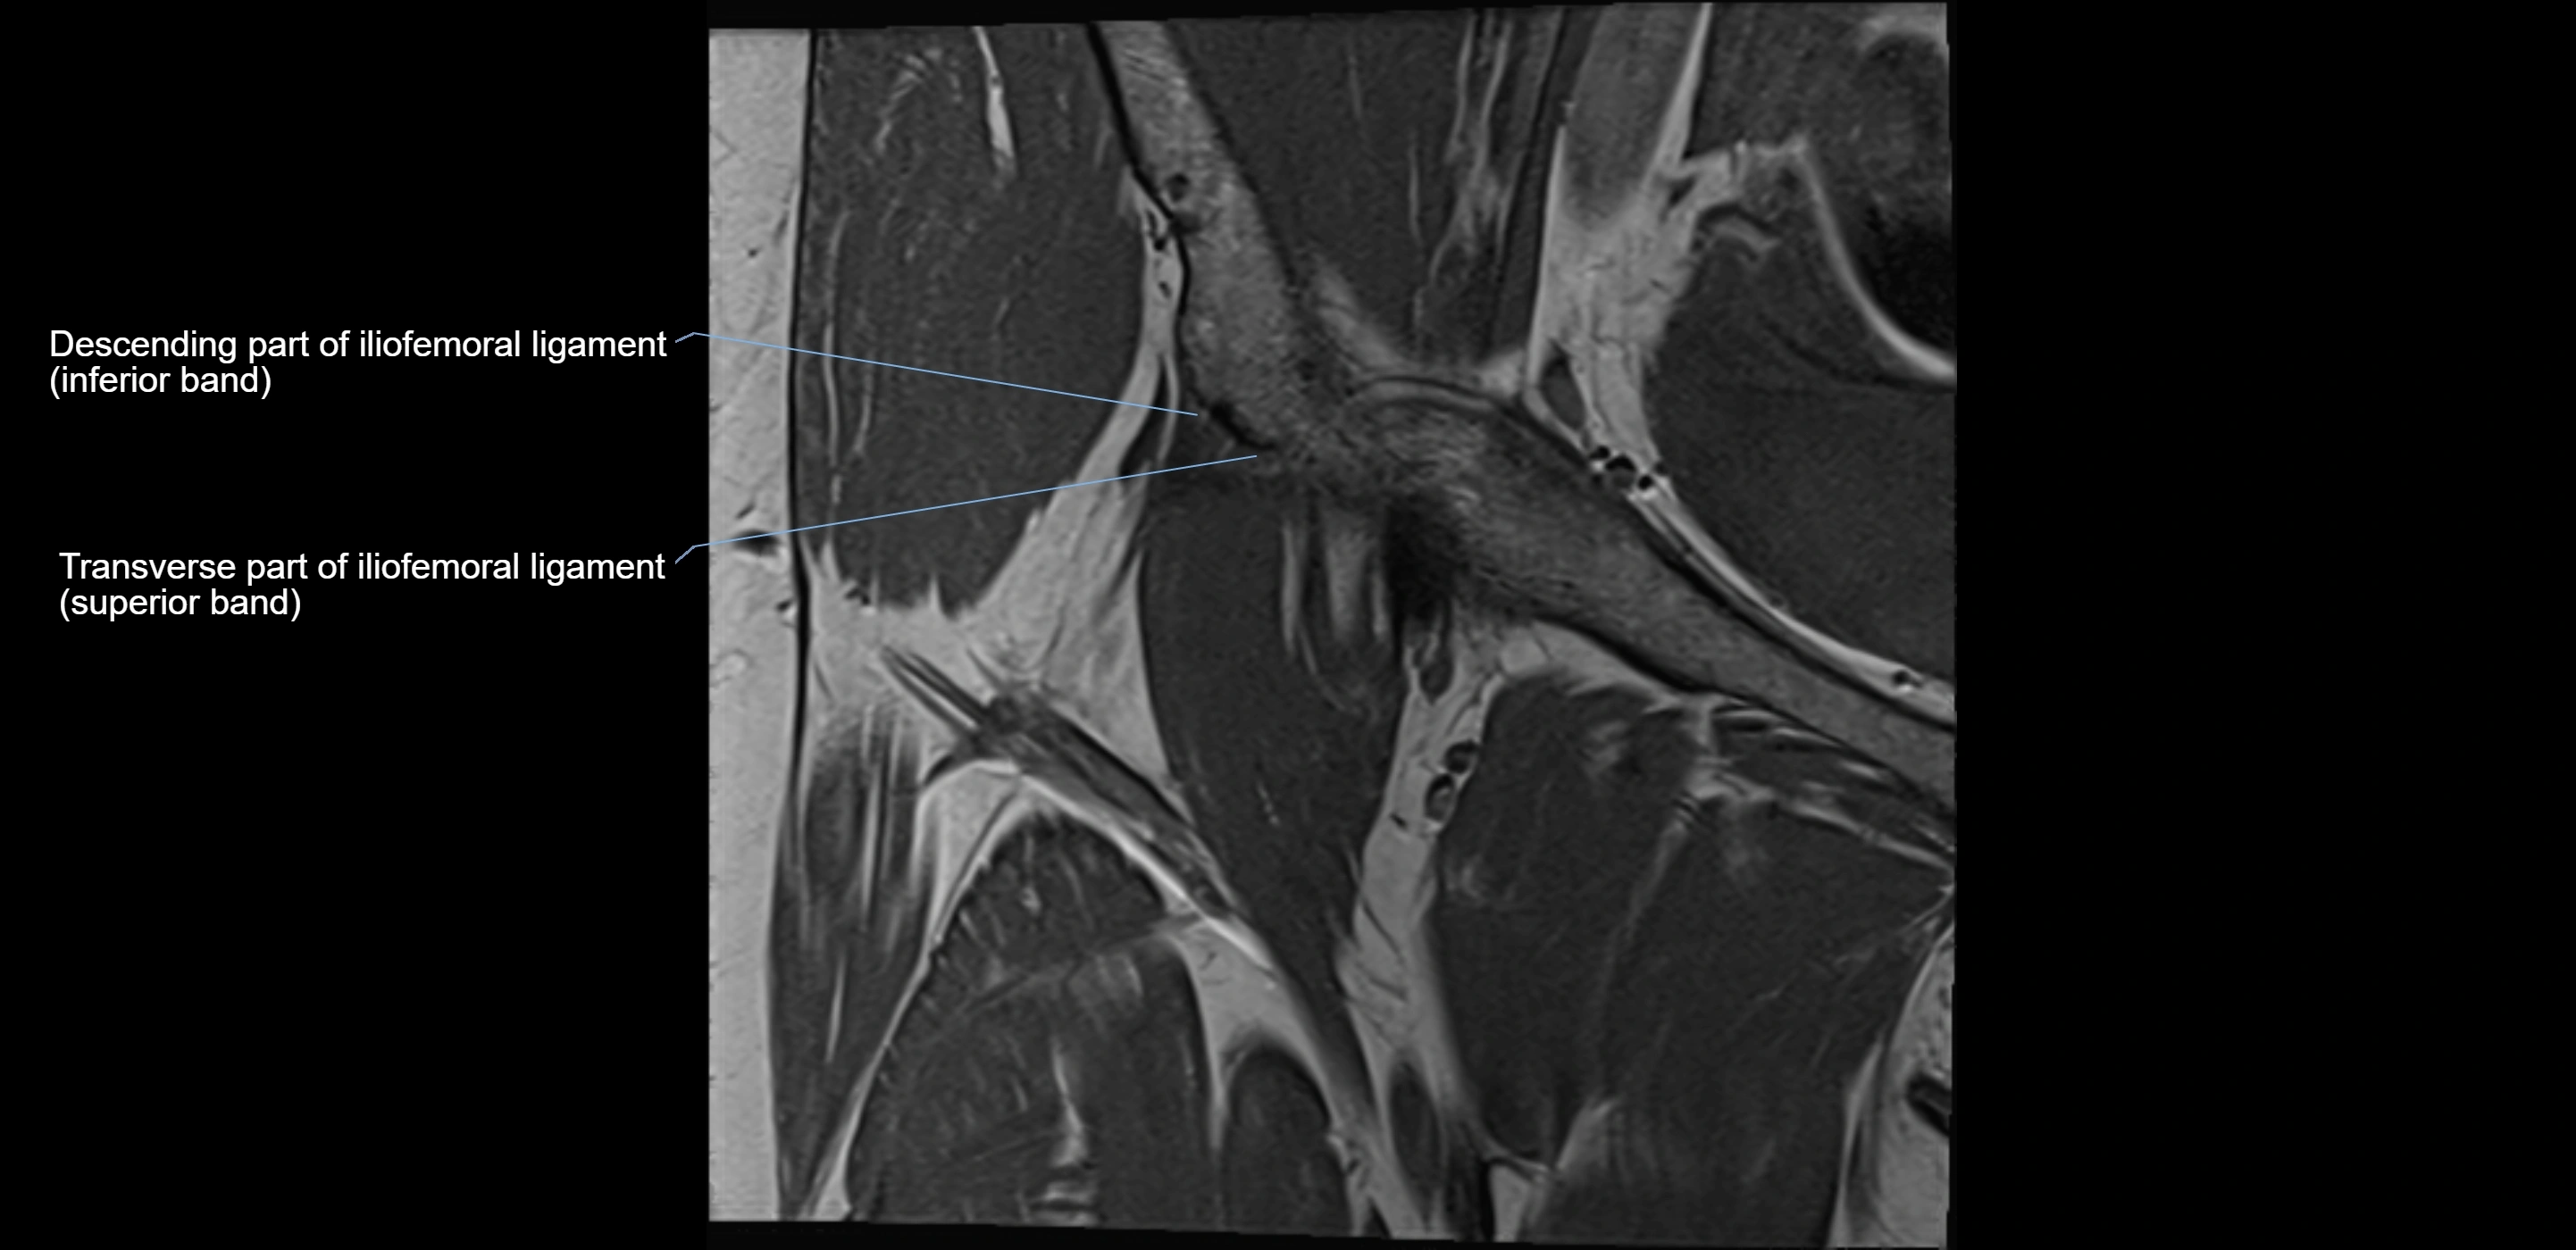

MRI image

image